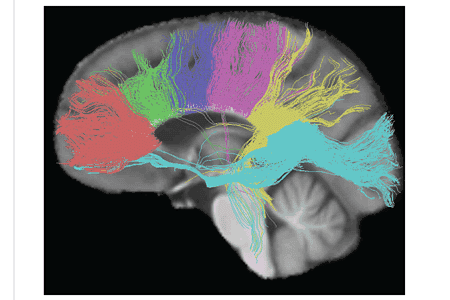

The size, amount of myelination, and density of the fibers in the subregions relate to the functions of the brain regions they connect.[8] Myelination is the process of coating neurons with myelin, which helps the transfer of information between neurons. The process is believed to occur until an individual's thirties with peak growth in the first decade of one's life.[9] Thinner, lightly myelinated fibers are slower conducting and they connect the association and prefrontal areas. Thicker and fast-conducting fibers connect the visual and motor areas.[10]

The tractogram pictured shows the nerve tracts from six segments of the corpus callosum, providing linking of the cortical regions between the cerebral hemispheres. Those of the genu are shown in coral; of the premotor, green; of the sensory-motor, purple; of the parietal, pink; of the temporal, yellow; and of the splenium, blue.[11]

Thinner axons in the genu connect the prefrontal cortex between the two halves of the brain; these fibers arise from a fork-like bundle of fibers from the tapetum, the forceps minor. Thicker axons in the trunk of the corpus callosum interconnect areas of the motor cortex, with proportionately more of the corpus callosum dedicated to supplementary motor regions including Broca's area. The splenium communicates somatosensory information between the two halves of the parietal lobe and the visual cortex at the occipital lobe. These are the fibers of the forceps major.[12][13]